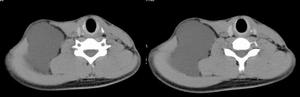

冠狀軸(二)面plane:按照軸線可將人體或器官切成不同的切面,以便從不同角度觀察某些結構。典型的切面有:矢狀面sagittalplane,是沿矢狀軸方向所做的切面,它是將人體分為左右兩部分的縱切面,如該切面恰通過人體的正中線,則叫做正中矢狀面mediansigittalplane;冠狀面或額狀面coronalplaneorfrontalplane,是沿冠狀軸方向所做的切面,它是將人體分為前後兩部的縱切面,與矢狀面和水平面相垂直;水平面或橫切面horizontalplaneortransverseplane,為沿水平線所做的橫切面,它將人體分為上下兩部,與上述兩個縱切面相垂直。須要注意的是,器官的切面一般不以人體的長軸為準而以其本身的長軸為準,即沿其長軸所做的切面叫縱切面longitudinalsection而與長軸垂直的切面叫橫切面transversesection。